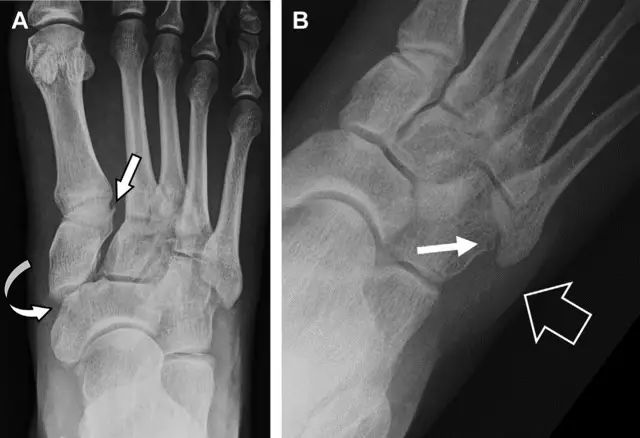

与跗跖关节韧带相关的骨折常由旋前或旋后的跖屈损伤引起。尽管跗跖关节骨折脱位仅占所有骨折的 0.2%,但是约 20% 的这些骨折在初次检查时被漏诊。初次 X 片可能示正常,但是负重位 X 线片常常提示脱位或半脱位。

典型表现:第二跖骨底和内侧楔骨之间的骨折碎片,跖骨间间隙增宽(图 8)。脱位亦可发生在舟骨-内侧楔骨关节,导致另一种变异的跗跖关节损伤(图 9A)。此外,骰骨的小块皮质撕脱在足部斜位片上可清晰显示(图 9B)。

图 8 从马上摔落的患者,跗跖关节骨折。A 正位片示内侧楔骨旁边的小骨折碎片(箭头),第二跖骨底向外半脱位;B 负重位侧位片示第二跖骨相对中间楔骨向背侧轻微移位(长方形);C STIR 序列 MRI 图像示跗跖关节韧带断裂(箭头),第一至第三跖骨、内侧楔骨及中间楔骨均骨髓水肿

图 9 变异的跗跖关节骨折。A 另一种类型的跗跖关节损伤,中间楔骨向内侧半脱位(弧形箭头),从而使第一、第二跖骨间间隙变宽,需注意,骨折在靠近内侧楔骨处(箭头);B 外侧跗跖关节损伤伴随从骰骨跖骨韧带的骰骨撕脱(箭头),需注意,第五跖骨底近端处存在软组织水肿(空箭头)